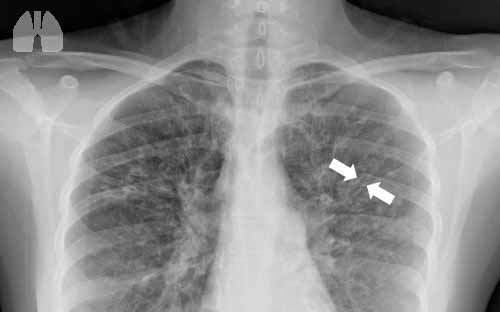

Aim: To evaluate the effect of inhaled tobramycin and colistin on eradication of Pa in patients with NCFB.

Methods: Fifty two patients were studied (33 women), mean age58.6+15.2 years, with >104 CFU of Pa/ ml in sputum culture. All patients received ciprofloxacin 750 mg bid for 14 days. They were then randomized in 3 groups and received: Tobramycin (Tobi, Novartis) 300mgx2 (group A, n=17), Colistimethate sodium (Colistin, Norma) 1MUx2 (group B, n=18), placebo N/S 0.9% 4ccx2 (group C, n=17). Administration was done through Pari LC Plus jet nebulizer for 3 months. Sputum culture, volume and purulence, dyspnea, spirometry and SaO2 were estimated before and after treatment.